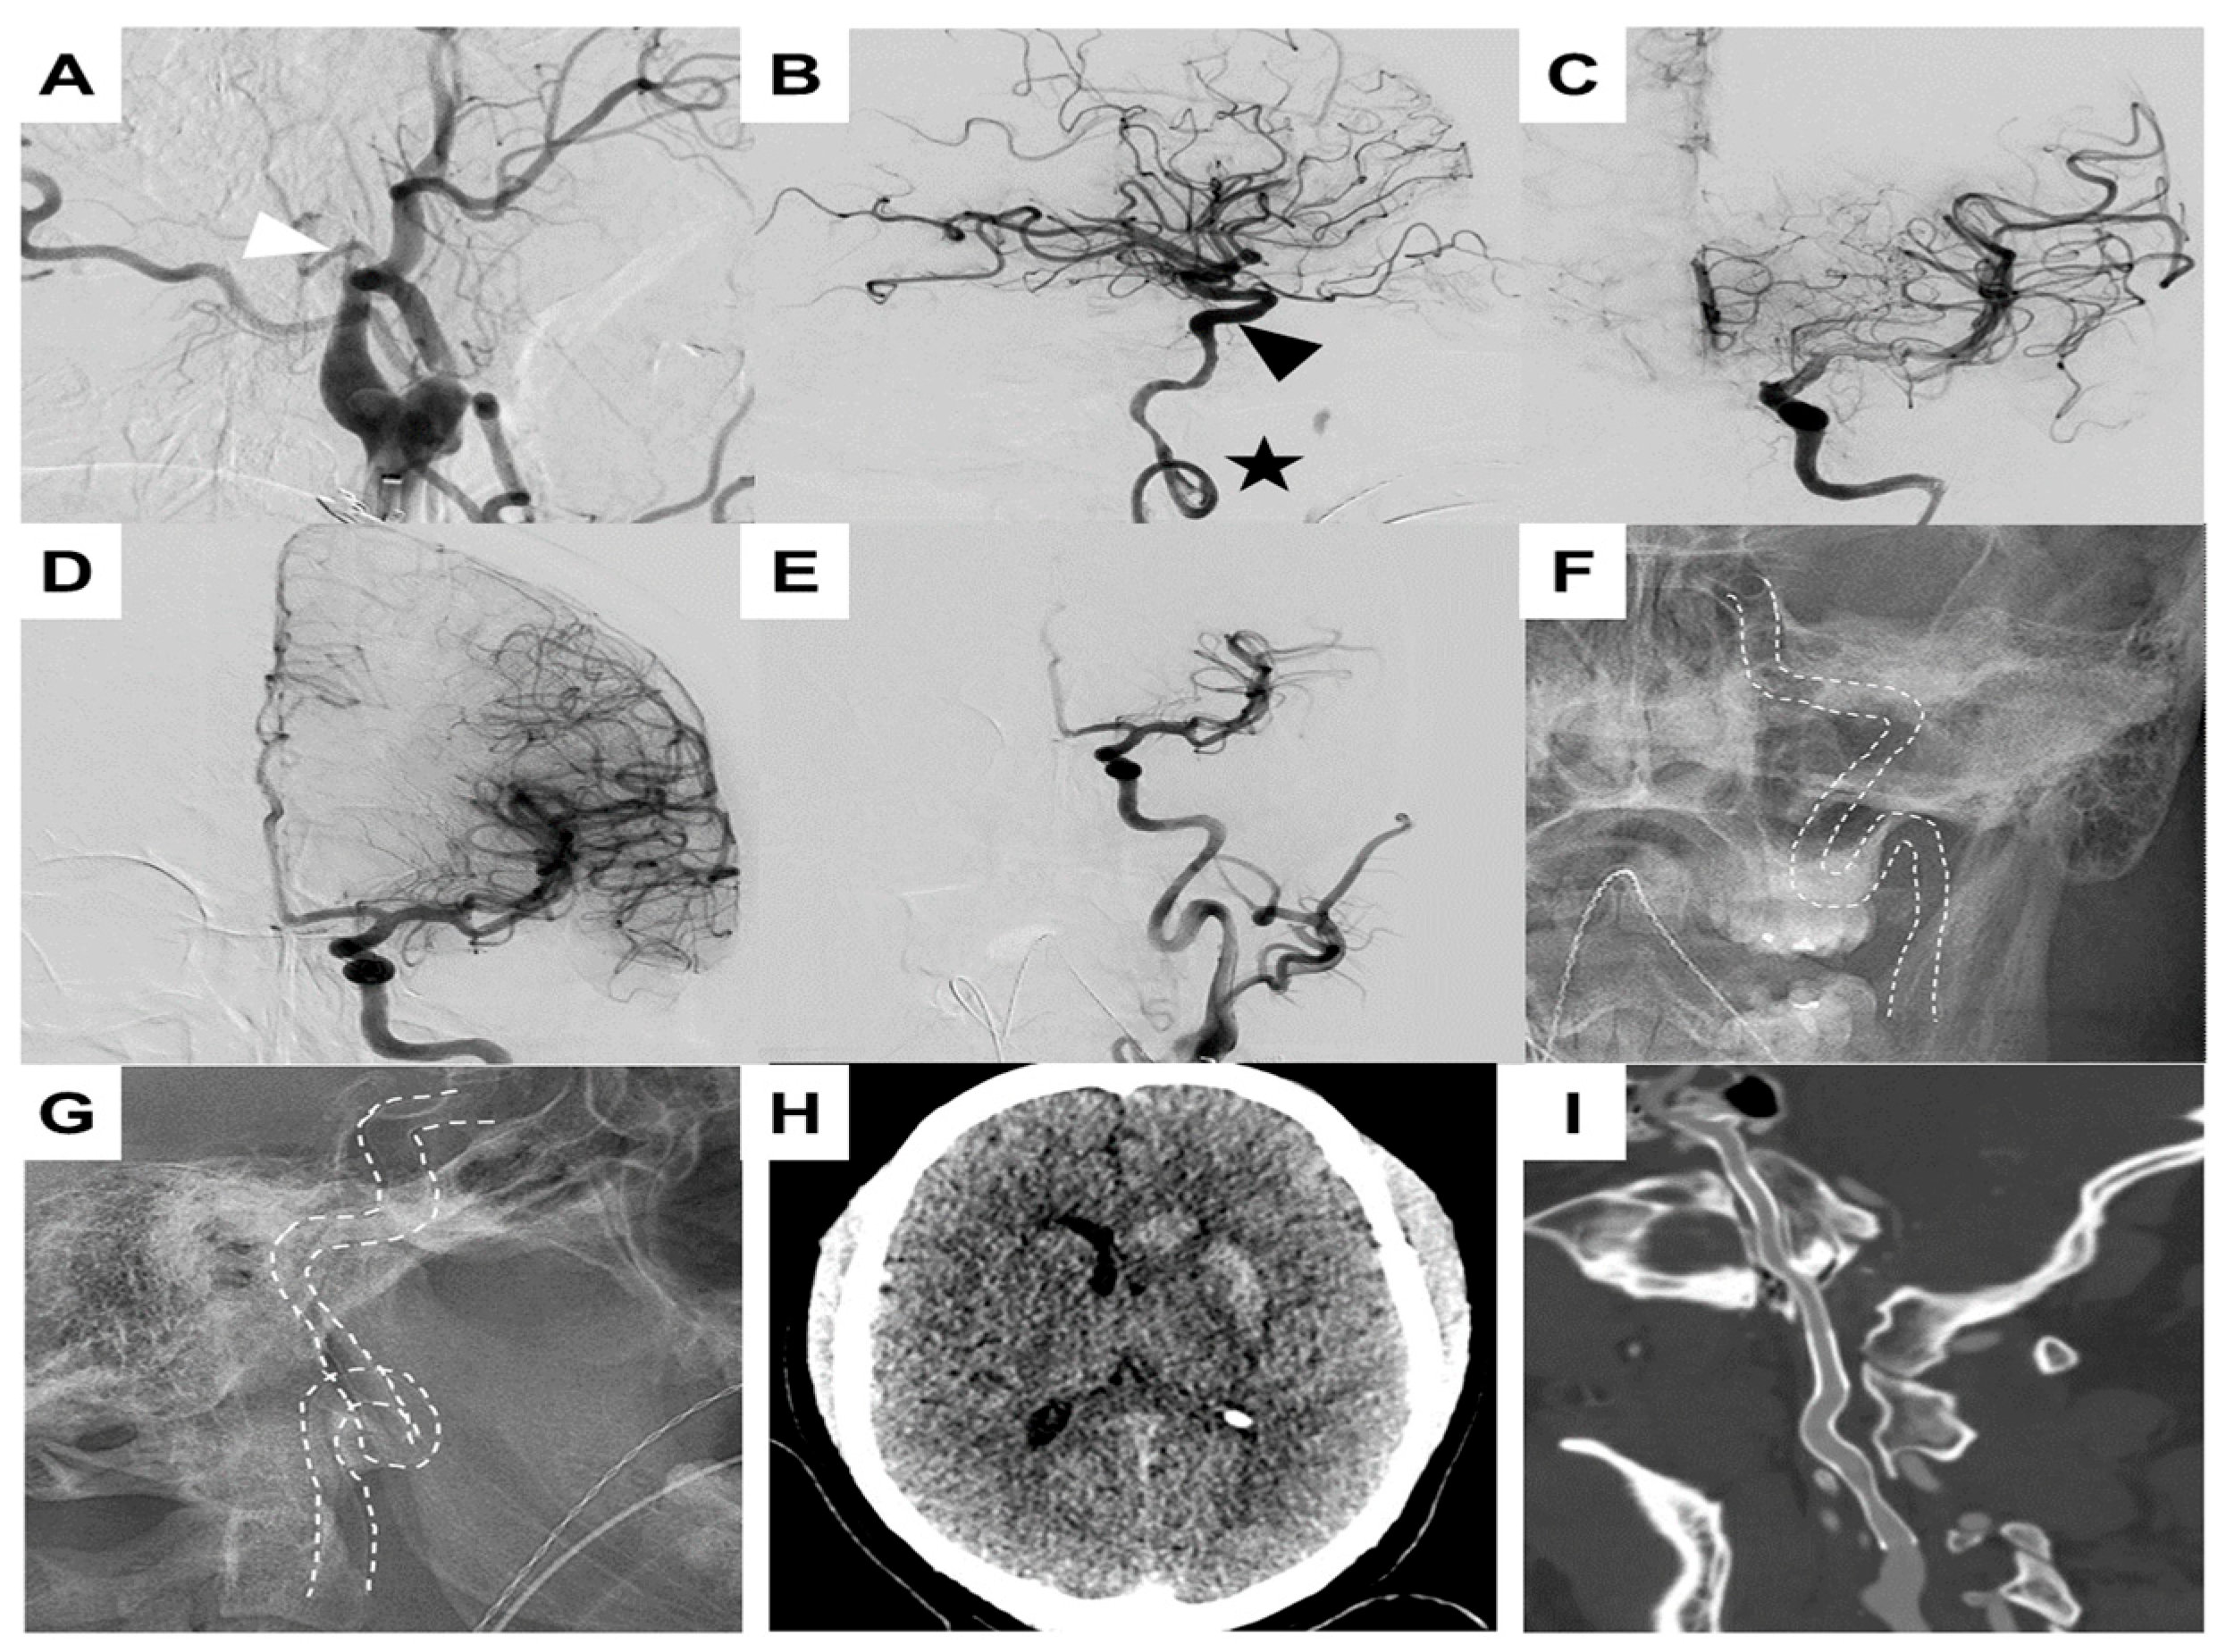

Case Illustration